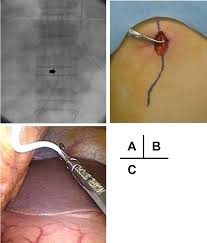

Surgical Findings A Ventriculoperitoneal Vp Shunt Catheter Arrow Download Scientific Diagram

Ventriculoperitoneal Shunt Tubing Sutured To Ptfe Mesh Extracorporeally Download Scientific Diagram